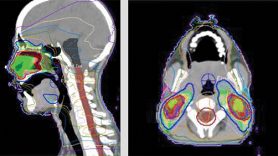

Los radiooncólogos del MD Anderson combinan la resonancia magnética, la tomografía por emisión de positrones y la tomografía computarizada para definir la extensión de la enfermedad. De esta manera, la radiación puede dirigirse al tumor sin comprometer las estructuras normales. Además, para adaptar la dosis al área deseada, se utiliza radioterapia de intensidad modulada (IMRT). Antes de cada sesión de tratamiento, se vuelve a tomar imágenes para comprobar la respuesta del tumor a los tratamientos anteriores y, si es necesario, precisar aún más el área deseada.